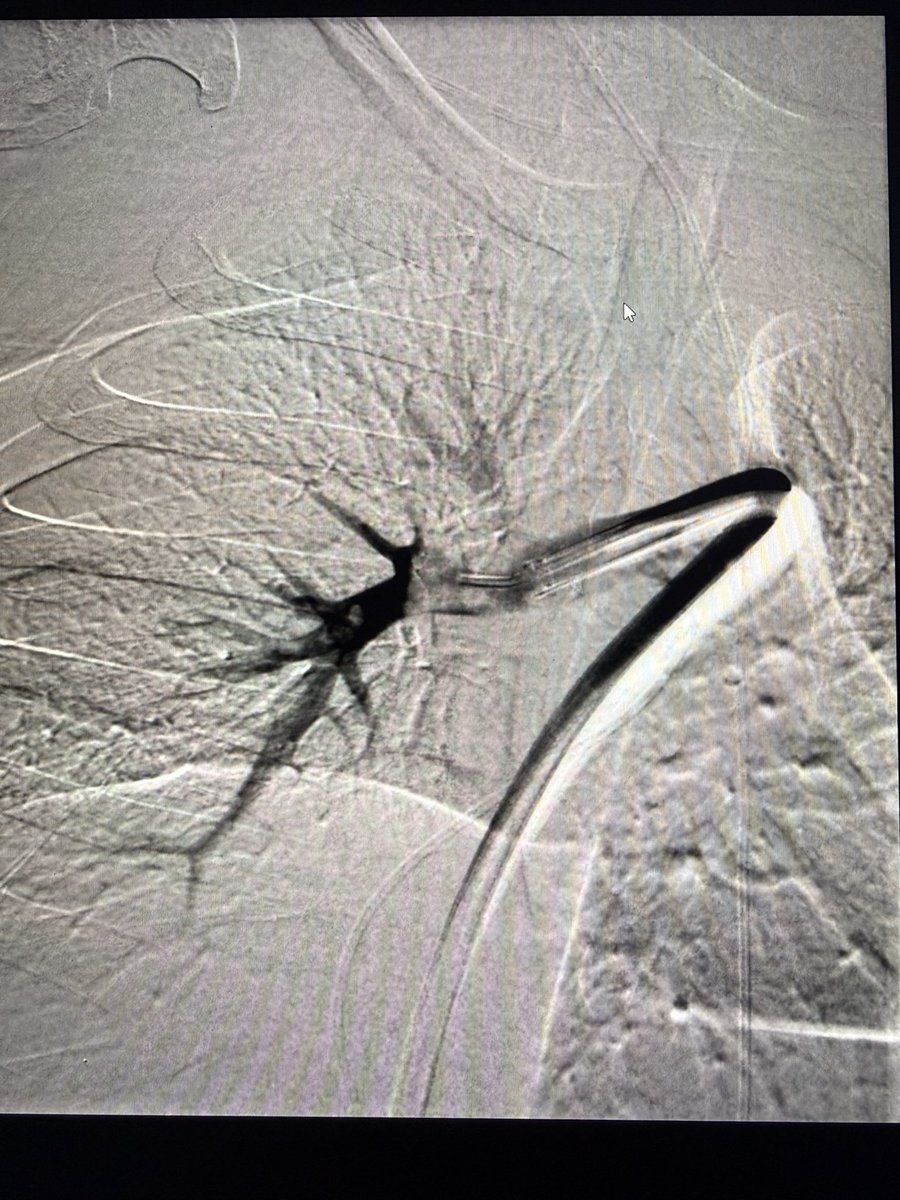

In the spirit of chronic clot (@DrJayMohan) - just pulled out the largest chronic PE I’ve encountered.

Tough situation w/ peds patient, malignancy and prolonged hospitalization with delayed diagnosis.

PA angle also very difficult to deal with.

Well compensated but symptomatic with chest pressure improving immediately.

AC wasn’t going to touch this, guarded prognosis overall but I’d argue better out than in

Controversial? What are your thoughts?